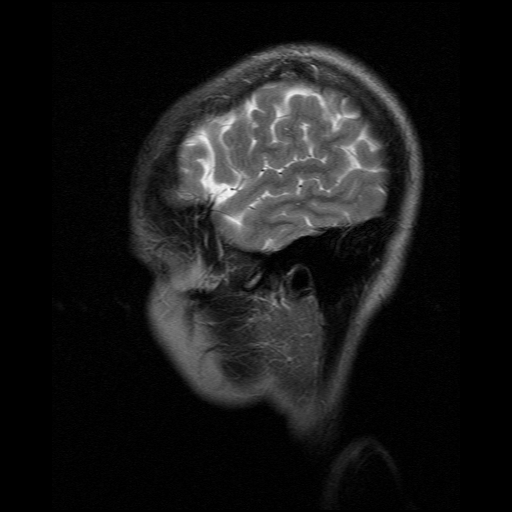

Encefalo: immagini pesate in T2

Selezione di immagini pesate T2